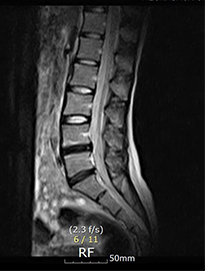

디스크내장증을 다른 말로 블랙디스크(black disc)라고 부르기도 하는데, MRI 검사 영상을 보면 디스크 부분이 검게 보이기 때문에 블랙디스크라고 부릅니다. 디스크 내의 수분이 빠지면서 탄성이 떨어지고 퇴행이 진행되어 검게 보이는 것인데요. 이처럼 아직 디스크가 탈출하지 않아 방사통이나 저림 증상이 없다고 하더라도 이미 퇴행이 진행된 상태라 이는 퇴행성 디스크의 일종이라 볼 수 있습니다. 하지만 중요한 것은 까맣게 변성된 디스크가 직접 통증을 일으키는 원인이 아니고 허리 근육 기능이 약화되고 심각한 기능적인 문제가 통증의 직접적인 원인입니다.

디스크내장증은 디스크가 탈출된 것이 아닌 디스크만 퇴행된 것이므로, MRI영상으로 보면 신경이 지나가는길이 깨끗하다는 것이 특징입니다.